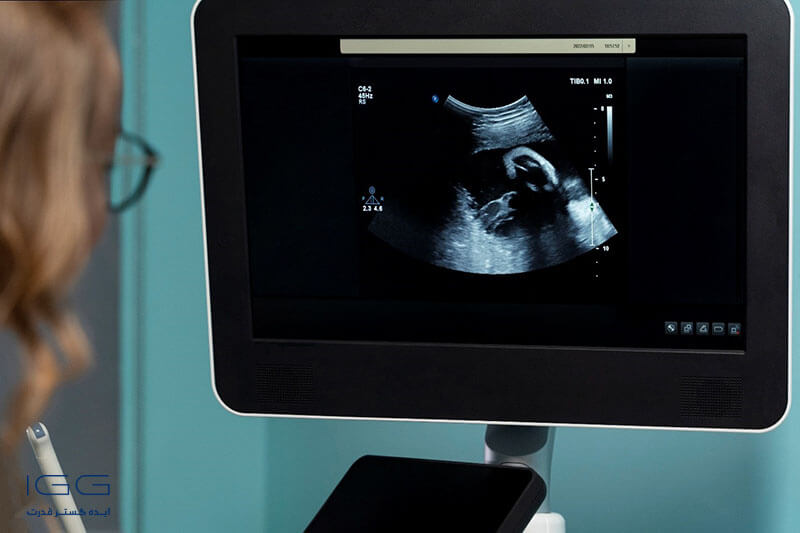

سونوگرافی یکی از تستهای تشخیصی و غربالگری بسیار مهم و حیاتی در دوران بارداری بانوان به شمار میرود و برای بررسی سلامت جنین و مادر، طی هفتههای مختلفی از دوران بارداری انجام میشود. برای آشنایی بیشتر با سونوگرافی و ضرورت آن برای مادر و جنین در دوران بارداری، توصیه میکنیم تا انتهای این مطلب همراه ما باشید.

چرا سونوگرافی در بارداری ضروری است؟

حتماً این سوال حداقل یکبار ذهن شما را به خود درگیر کرده است که چرا سونوگرافی در بارداری مهم است؟ در پاسخ میتوان به مزایای فوق العادهی سونوگرافی در دوران بارداری اشاره کرد:

- سونوگرافی سلامت جسمی جنین مانند سلامت قلب و اندامها را معاینه میکند.

- برای بررسی سلامتی رحم و دهانه رحم در مادر نیز مفید است.

- سونوگرافی بارداری داخل یا خارج رحم را تشخیص میدهد.

سونوگرافی مهمترین تست غربالگری در دوران بارداری است که پزشکان متخصص زنان و زایمان را از بابت سلامت دهانه رحم و سلامت جسمی و اندامی جنین مطمئن میسازد. به کمک سونوگرافی پزشکان میتوانند تمامی اختلالات اندامی، قلبی و عروقی یا حتی کروموزومی در جنین را تشخیص دهند.